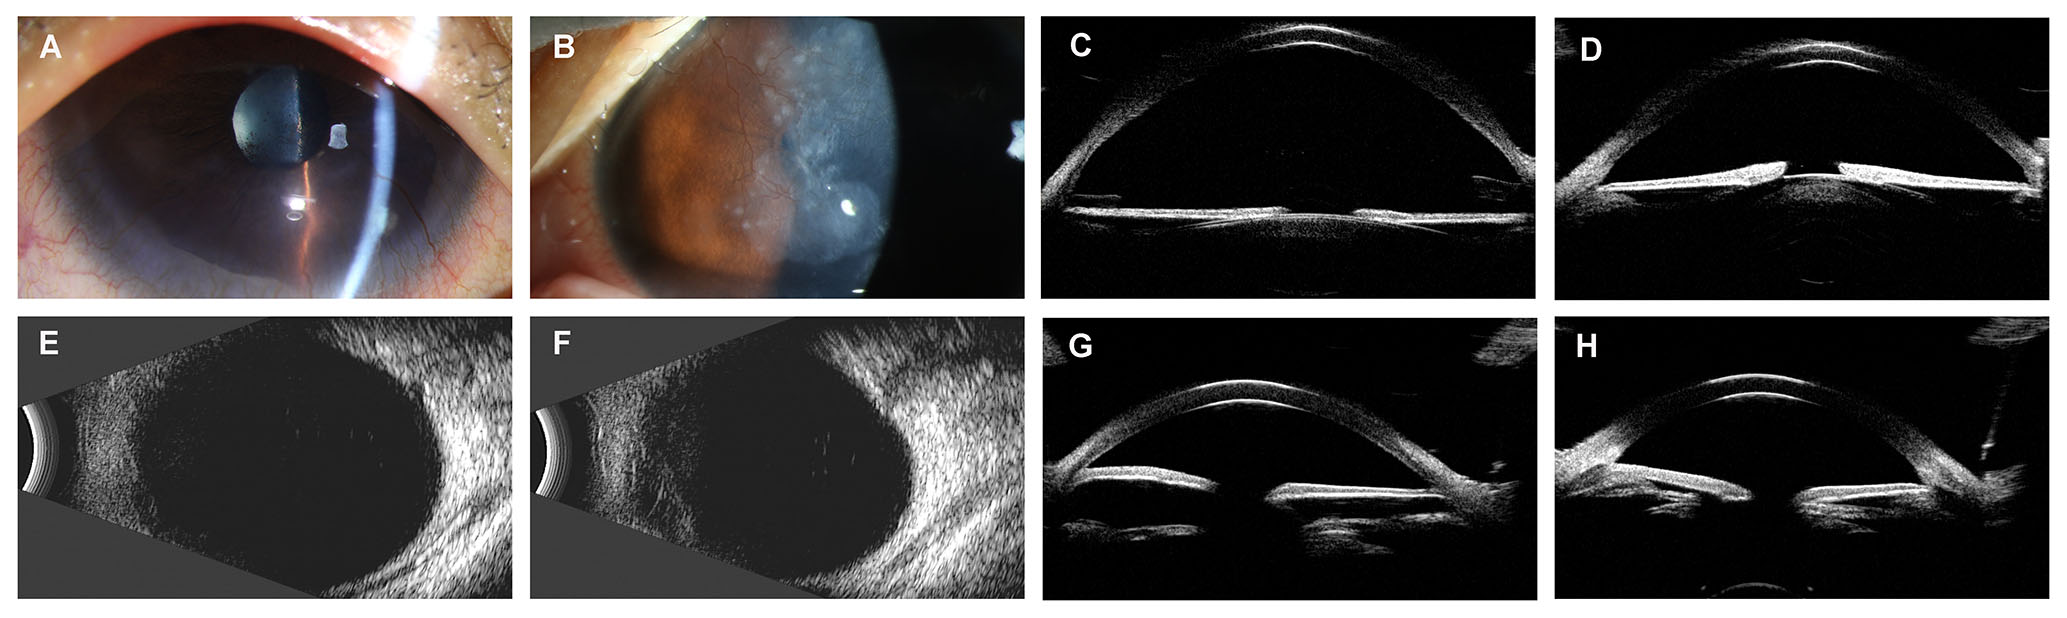

Figure 5. Ophthalmic examination instruments reveal the clinical manifestations of illustrative cases. A: Anterior segment photograph of the right eye of illustrative case 1 showed mild cortical cataract. B: Anterior segment photograph of the left eye of illustrative case 1 showed corneal pannus. C: UBM photograph of the right eye of illustrative case 1 showed open angle. D: UBM photograph of the left eye of illustrative case 1 showed open angle. E: B-scan ultrasound of the right eye of illustrative case 2 indicated a large cup. F: B-scan ultrasound of the left eye of illustrative case 2 indicated normal result. G: UBM photograph of the right eye of illustrative case 2 showed closed angle. H: UBM photograph of the left eye of illustrative case 2 showed open angle.